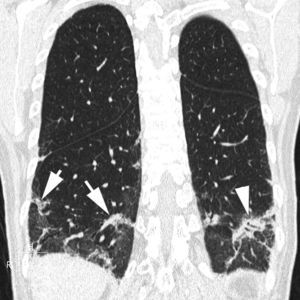

En la TCAR, la fase aguda de la AAE se caracteriza por la presencia de un patrón pulmonar difuso en «vidrio deslustrado», un patrón nodulillar o un patrón mixto, asociado muchas veces a áreas parcheadas de atrapamiento aéreo. En las fases crónicas, la presencia de un patrón reticular con desestructuración y retracción de los ejes broncovasculares refleja la presencia de fibrosis. Es frecuente el hallazgo asociado de áreas focales de atrapamiento aéreo (fig. 12)51.

Imagen TCAR centrada en lóbulos superiores en un paciente con alveolitis alérgica extrínseca en fase crónica, que destaca la presencia de opacidades reticulares, bronquiectasias de tracción y «vidrio deslustrado» (flechas), asociado a áreas focales de atrapamiento aéreo en lóbulo superior izquierdo (cabezas de flecha).